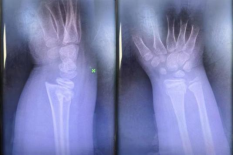

整个复位过程在团队的默契配合下顺利完成,术后患儿疼痛显著缓解,随即予以稳妥的外固定处理。复查X线片显示,骨折端对位对线明显改善,达到功能复位标准。安浩医生随后向家属详细交代了家庭护理要点、观察事项及康复指导,并安排次日返院复查。